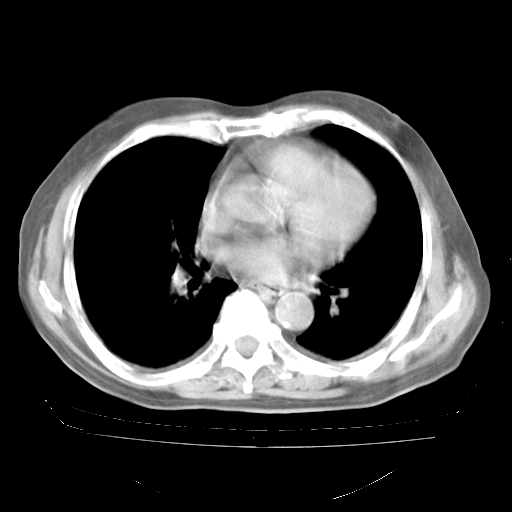

4月28日肺部CT——再次出现类似去年5月9日——透光度降低,“间质性”改变。

4月28日肺部CT——再次出现类似去年5月9日——磨玻璃样、间有“粟粒样”改变。

4月28日肺部CT